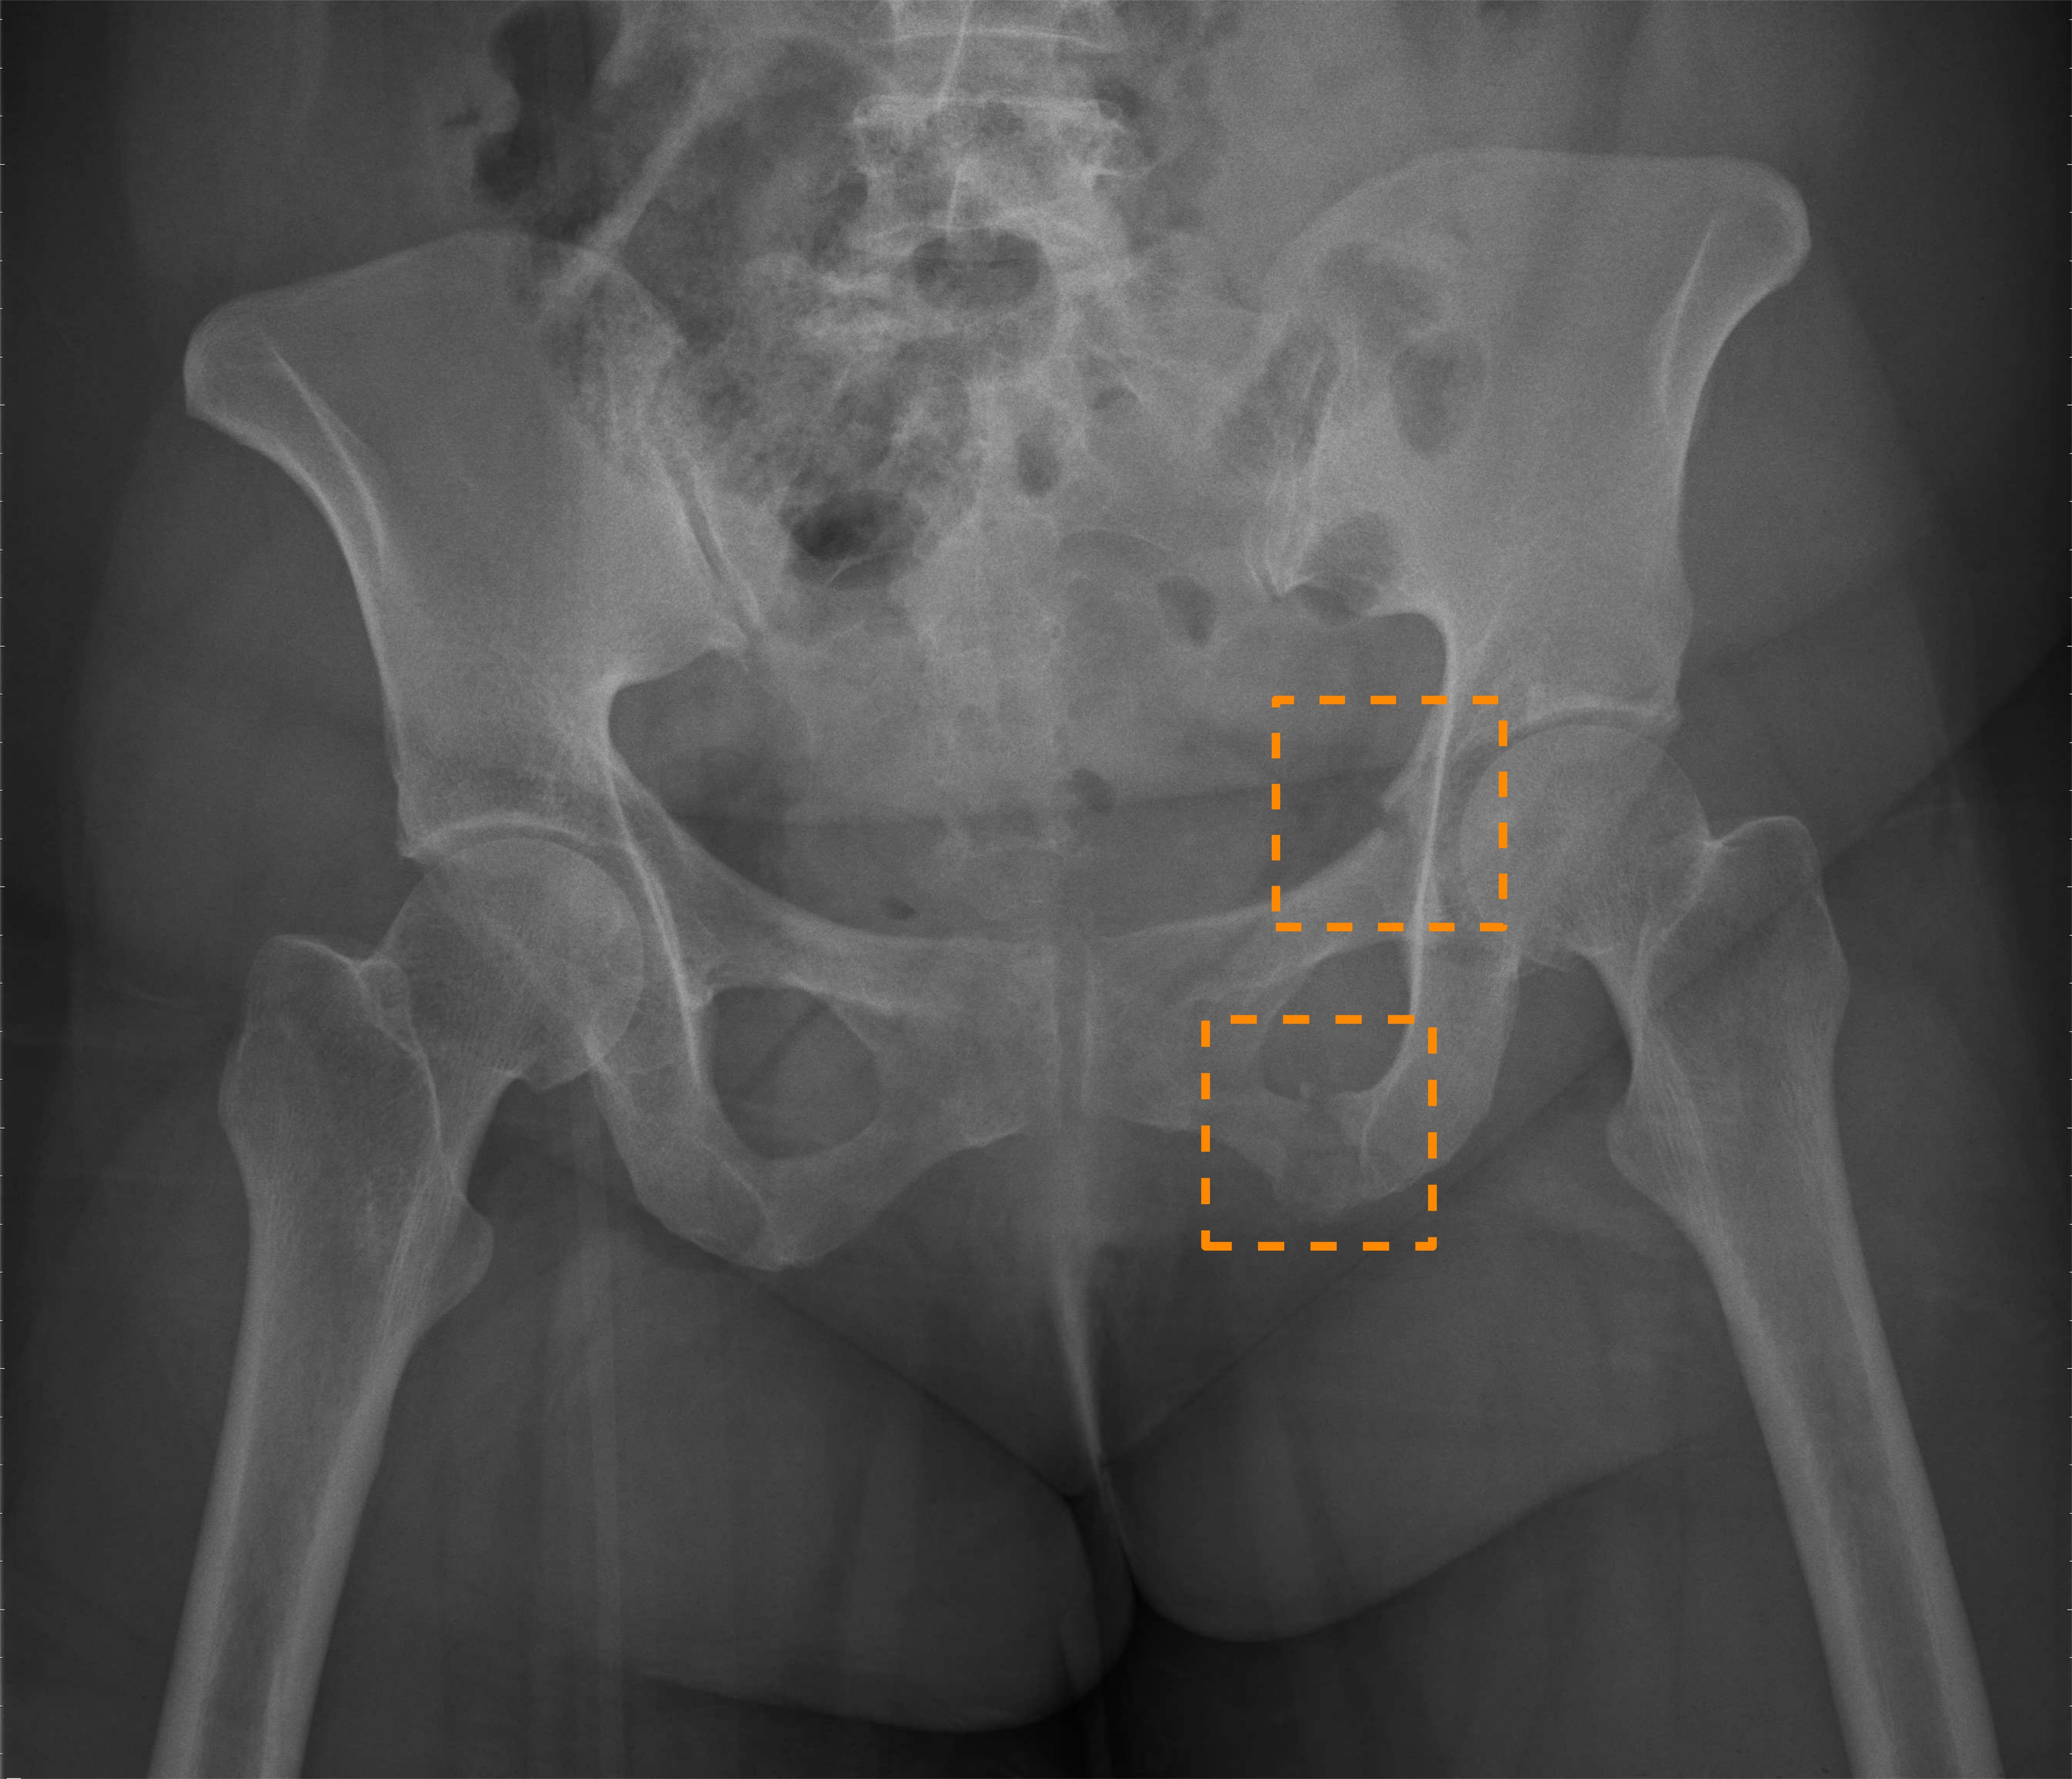

Nonetheless, the above prior work all only focuses on diagnosing hip fractures and does not attempt to classify the more complex pelvic fractures (fractures in three pelvic bones: the ilium, ischium, and pubis). As Fig. 1 illustrates, the makeup of pelvis fractures is much more complex, as there are a large variety of possible types with very different visual patterns at various locations. In addition, pelvic bones overlap with the lower abdomen, further confounding image patterns. Finally, unlike hip fractures, which occur at the femoral neck/head, pelvic fractures can occur anywhere on the large pelvis, both increasing the aforementioned image pattern combinatorial complexity and precluding automatic \acROI extraction based on anatomy alone, such as was done in prior work [4]. Thus, while using \acROI-based classification is even more desirable for pelvic fractures, it is paradoxically more challenging to extract said \acpROI.